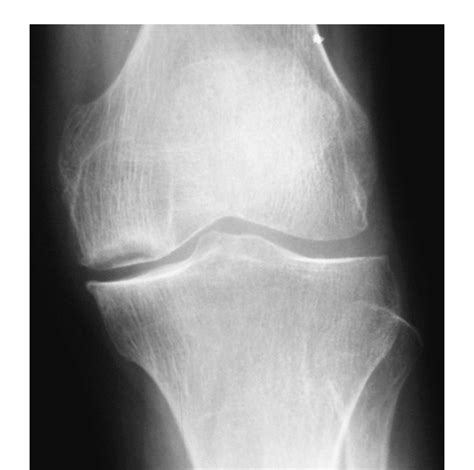

3、立即去医院做心电图和X线检查确诊,针对病因治疗。